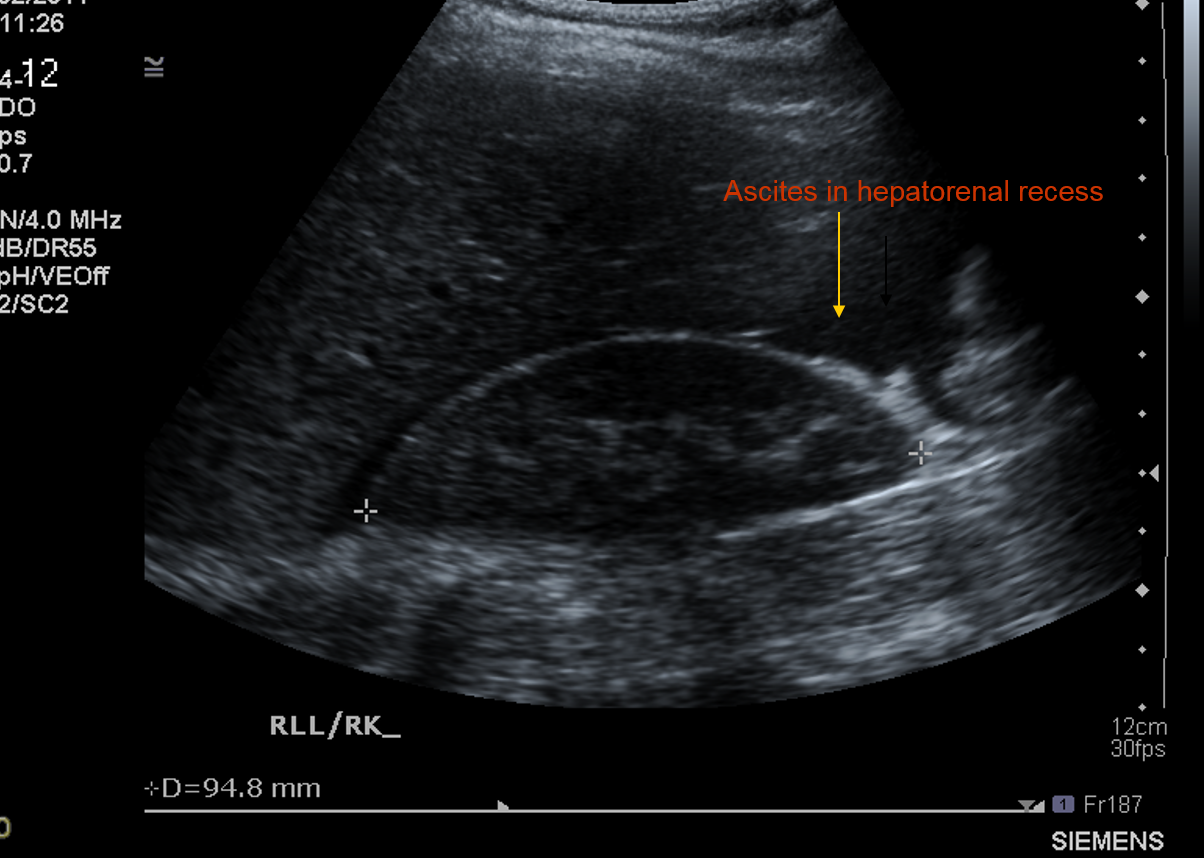

What pathological finding is shown here ?

What pathological sign is shown in this pic ?

Ascities in the hepatorenal recess due to an inflam reaction in the peritoneum